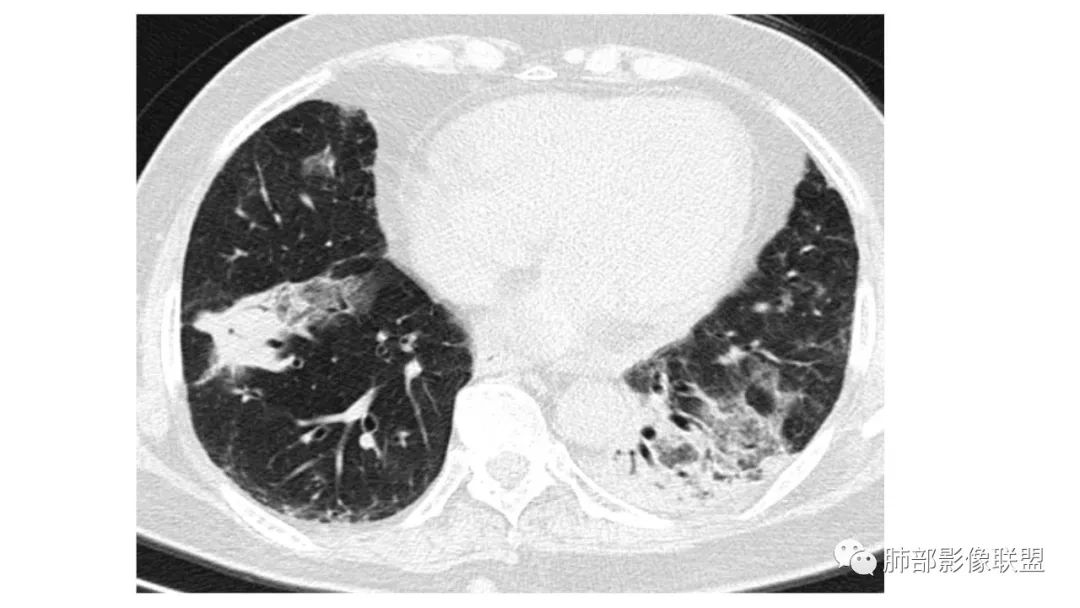

二、肺炎型

2、病灶常有一个主病灶,常位于下肺。后沿气道播散为多发病灶。

3、重力作用,叠瓦征。近叶间裂因重力效应,呈膨隆改变。

4、增强后不均匀强化,存在低强化区呈弱强化或无强化,因此可见“血管造影征。”血管毛糙与肺炎有统计学差异。

5、支气管粗细不均,呈“枯树枝征”,但与肺炎这一点鉴别不具有统计学差异。可发生支气管扩张

6、空腔形成,部分蜂窝状改变。

8、斑片常伴有结节,边缘清楚GGO或欠清楚。